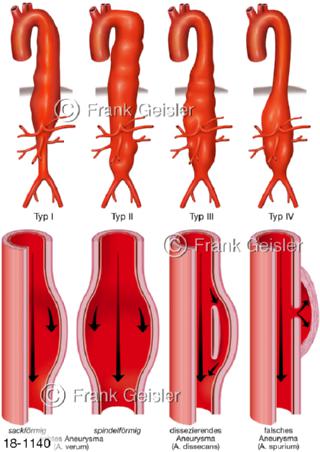

18-1140 Aorta, Formen Aneurysma, Aortenaneurysma